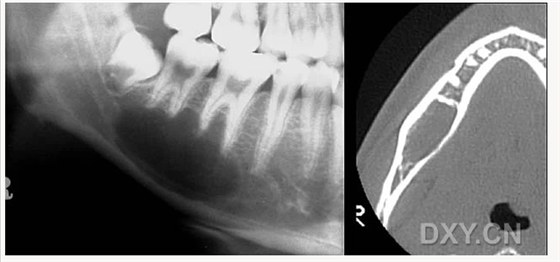

骨髓炎

含牙囊腫

頜骨骨折